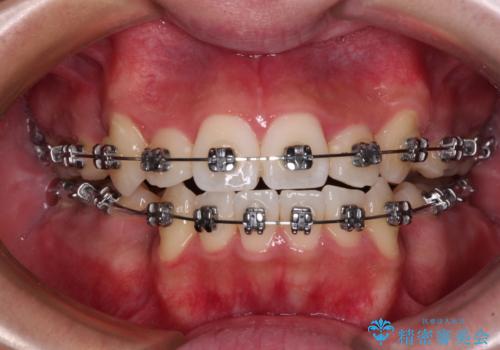

- メタルブラケット

- 治療期間

- 2年4ヶ月